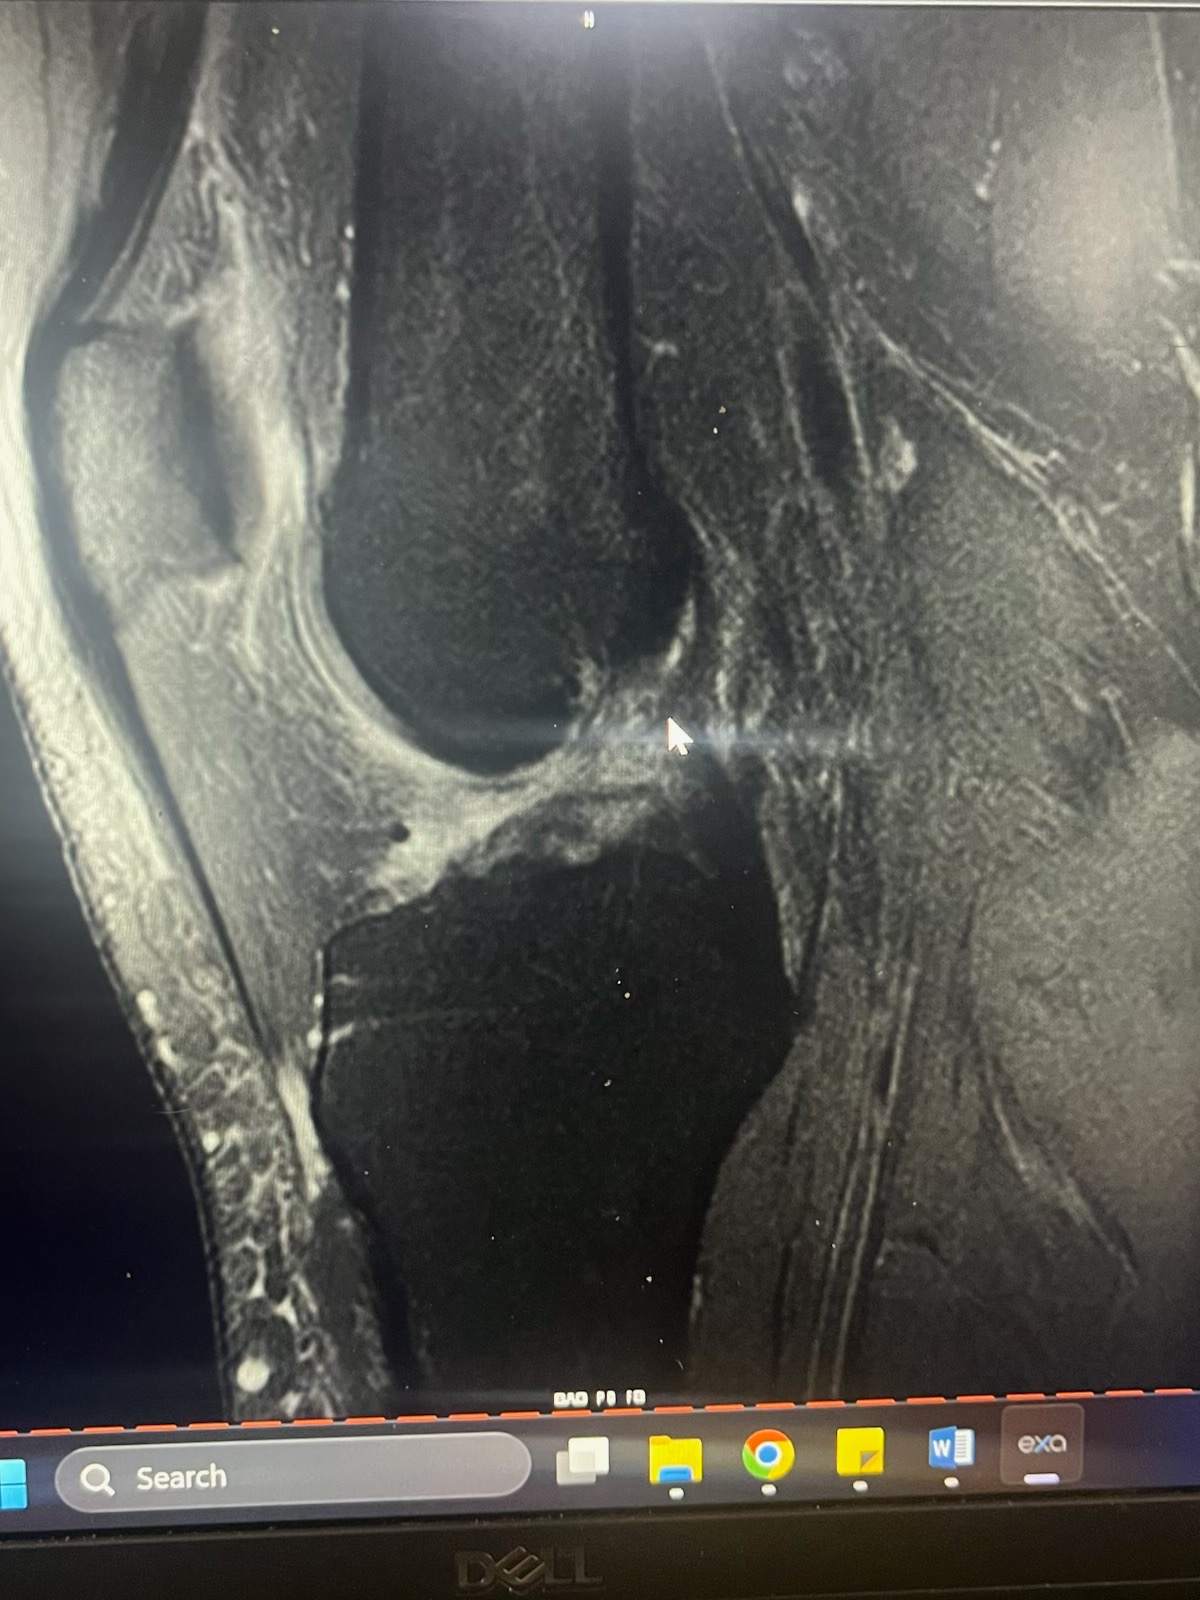

Some of you may know, but I took a fairly bad fall at work while in the kitchen and damaged my knee significantly enough to require surgery. Any money that is donated will be going towards medical costs that insurance won’t cover. On the 1st of July, I'm having an Arthroscopic Assisted ACL Reconstruction With Quadriceps Tendon Autograft, Medial And Lateral Meniscus Repair, and Osteochondral Lesion Repair With Cartiheal Agili-C Implant.

The attached photo is an MRI of my knee showing my ACL (or lack thereof lol)